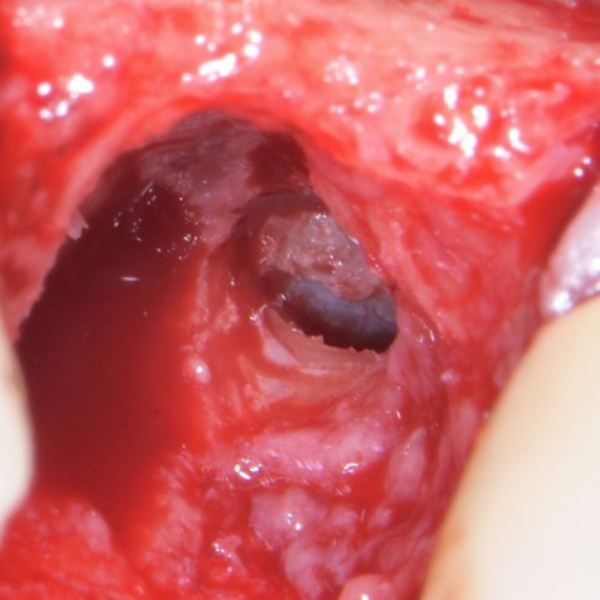

UL5 Extraction and Implant Placement

Patient suffered from a root fracture. Needed removal and to restore hard and soft tissue.